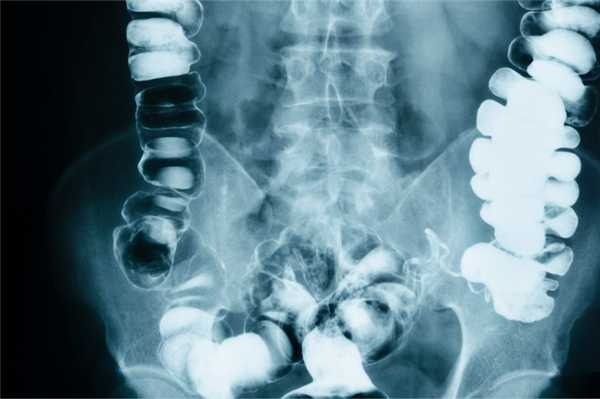

При обзорной рентгенографии органов брюшной полости в сроки до 24 ч начала заболевания отмечалась пневматизация петель тонкой кишки, единичные расширенные петли тонкой кишки с уровнем жидкости в них. У 11 (64,7%) пациентов, поступивших в сроки позднее 24 ч от начала заболевания, отмечались множественные расширенные петли тонкой кишки с уровнями жидкости в них по типу чаш Клойбера, а также уровень жидкости в желудке (гастростаз). Чувствительность метода составила 88%.

При обзорной рентгенографии брюшной полости определяются характерные кишечные арки (раздутая газом кишка с уровнями жидкости), чаши Клойбера (куполообразные просветления над горизонтальным уровнем жидкости), симптом перистости (наличие поперечной исчерченности кишки). Рентгеноконтрастное исследование ЖКТ применяется в затруднительных диагностических случаях. В зависимости от уровня кишечной непроходимости может использоваться рентгенография пассажа бария по кишечнику или ирригоскопия. Колоноскопия позволяет осмотреть дистальные отделы толстого кишечника, выявить причину обтурации кишки и в ряде случаев - разрешить явления острой кишечной непроходимости.

С помощью исследования кишечника специалист может обнаружить жидкости и газы, которые образуют «чаши» и «арки». На рентгенологическом снимке так называемые «чаши Клойбера» выглядят как газовые пузыри полукруглой формы. Картина чаши формируется, когда петля кишки содержит больше жидкости и небольшое количество газа, арки - наоборот. Чаша может трансформироваться в арку, а арка в чашу.

При кишечной непроходимости появляется сразу несколько чаш Клойбера, которые располагаются в центре брюшной полости, в районе петель тонкой кишки. На рентгенограмме это выглядит как вздутые участки кишки, заполненные жидкостью и газом.